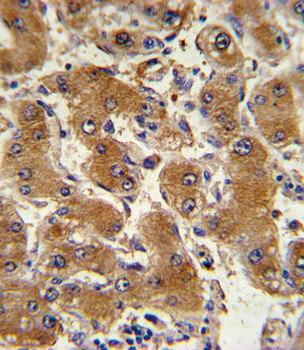

IHC analysis of COL6A1 using anti-COL6A1 antibody. COL6A1 was detected in a paraffin-embedded section of human gastric adenocarcinoma tissue. Heat mediated antigen retrieval was performed in EDTA buffer (pH8.0, epitope retrieval solution). The tissue section was blocked with 10% goat serum. The tissue section was then incubated with 2 µg/ml rabbit anti-COL6A1 Antibody overnight at 4°C. Biotinylated goat anti-rabbit IgG was used as secondary antibody and incubated for 30 minutes at 37°C. The tissue section was developed using Strepavidin-Biotin-Complex (SABC) with DAB as the chromogen.